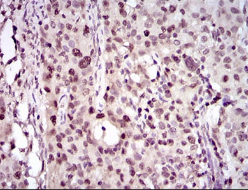

IHC    1/100 - 1/500